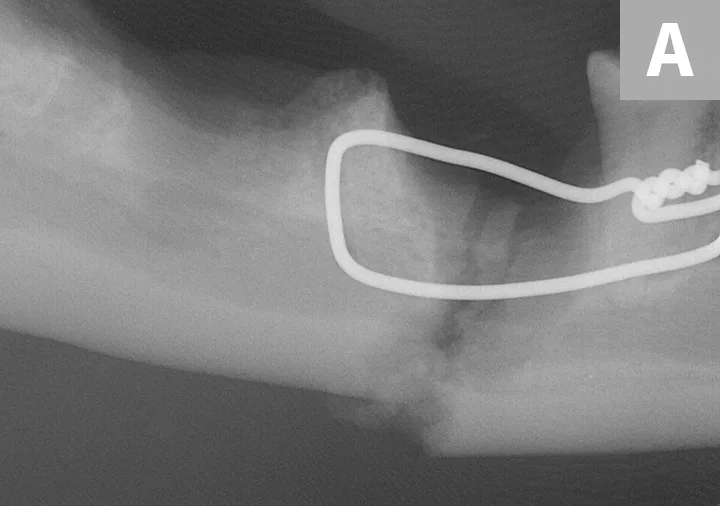

The patient was presented 7 weeks later for a recheck oral examination under general anesthesia (performed in the same manner as previously). Dental radiographs demonstrated healing of the fractures (Figure 4). The interfragmentary wires were removed via an intraoral approach, and postoperative intraoral radiographs were obtained to confirm adequate healing (Figure 5). The patient recovered uneventfully.

Postoperative intraoral dental radiographs of the right (A) and left (B) mandible following reduction and fixation with a single intraosseous wire on each side.